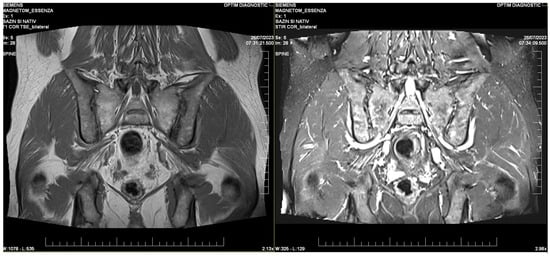

2.2. Progression and Diagnosis of Non-Radiographic Axial Spondylarthritis (2020)

2.3. Clinical Deterioration and Persistent Symptoms (June 2023)